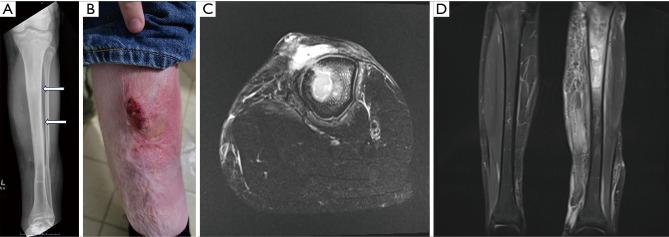

CASE DESCRIPTION

We present the case of a 16-year-old male with extensive left lower extremity osteomyelitis secondary to eight years after an open fracture to this leg was complicated by an infection with the same organism. Suboptimal therapy of his initial infection may have contributed to persistent, latent disease before recurrence years later. Evaluation for immunodeficiency was negative and he responded well to ciprofloxacin antibiotic therapy.

病例描述

我们报告一例16岁男性,其左下肢广泛骨髓炎继发于该腿部开放性骨折8年后,此次骨折因感染同一病原体而复杂化。他最初感染的治疗不充分可能导致了疾病持续存在、潜伏,直至数年之后复发。免疫缺陷评估为阴性,他对环丙沙星抗生素治疗反应良好。